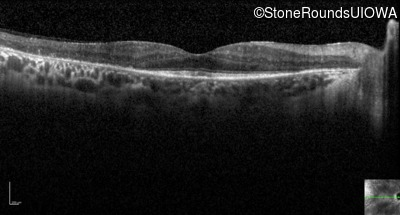

Optical Coherence Tomography - Left - 20/100

Exemplar / OCT Stack

OCT Stack